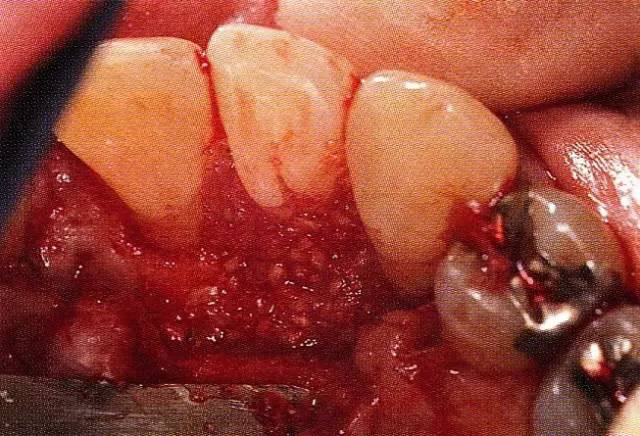

案例3   針對3壁性垂直性骨缺損使用非吸收性膜進行再生治療,再翻瓣時進行骨形態(tài)修整的病例。

▲圖7-1  左下6近中可觀察到3壁性垂直性骨缺損。此病例考慮到齦瓣供血關(guān)系,在前磨牙部位進行了減張切開,沒有進行縱切開。并利用刮治器、牙周外科用車針進行了徹底的骨缺損部位搔刮。